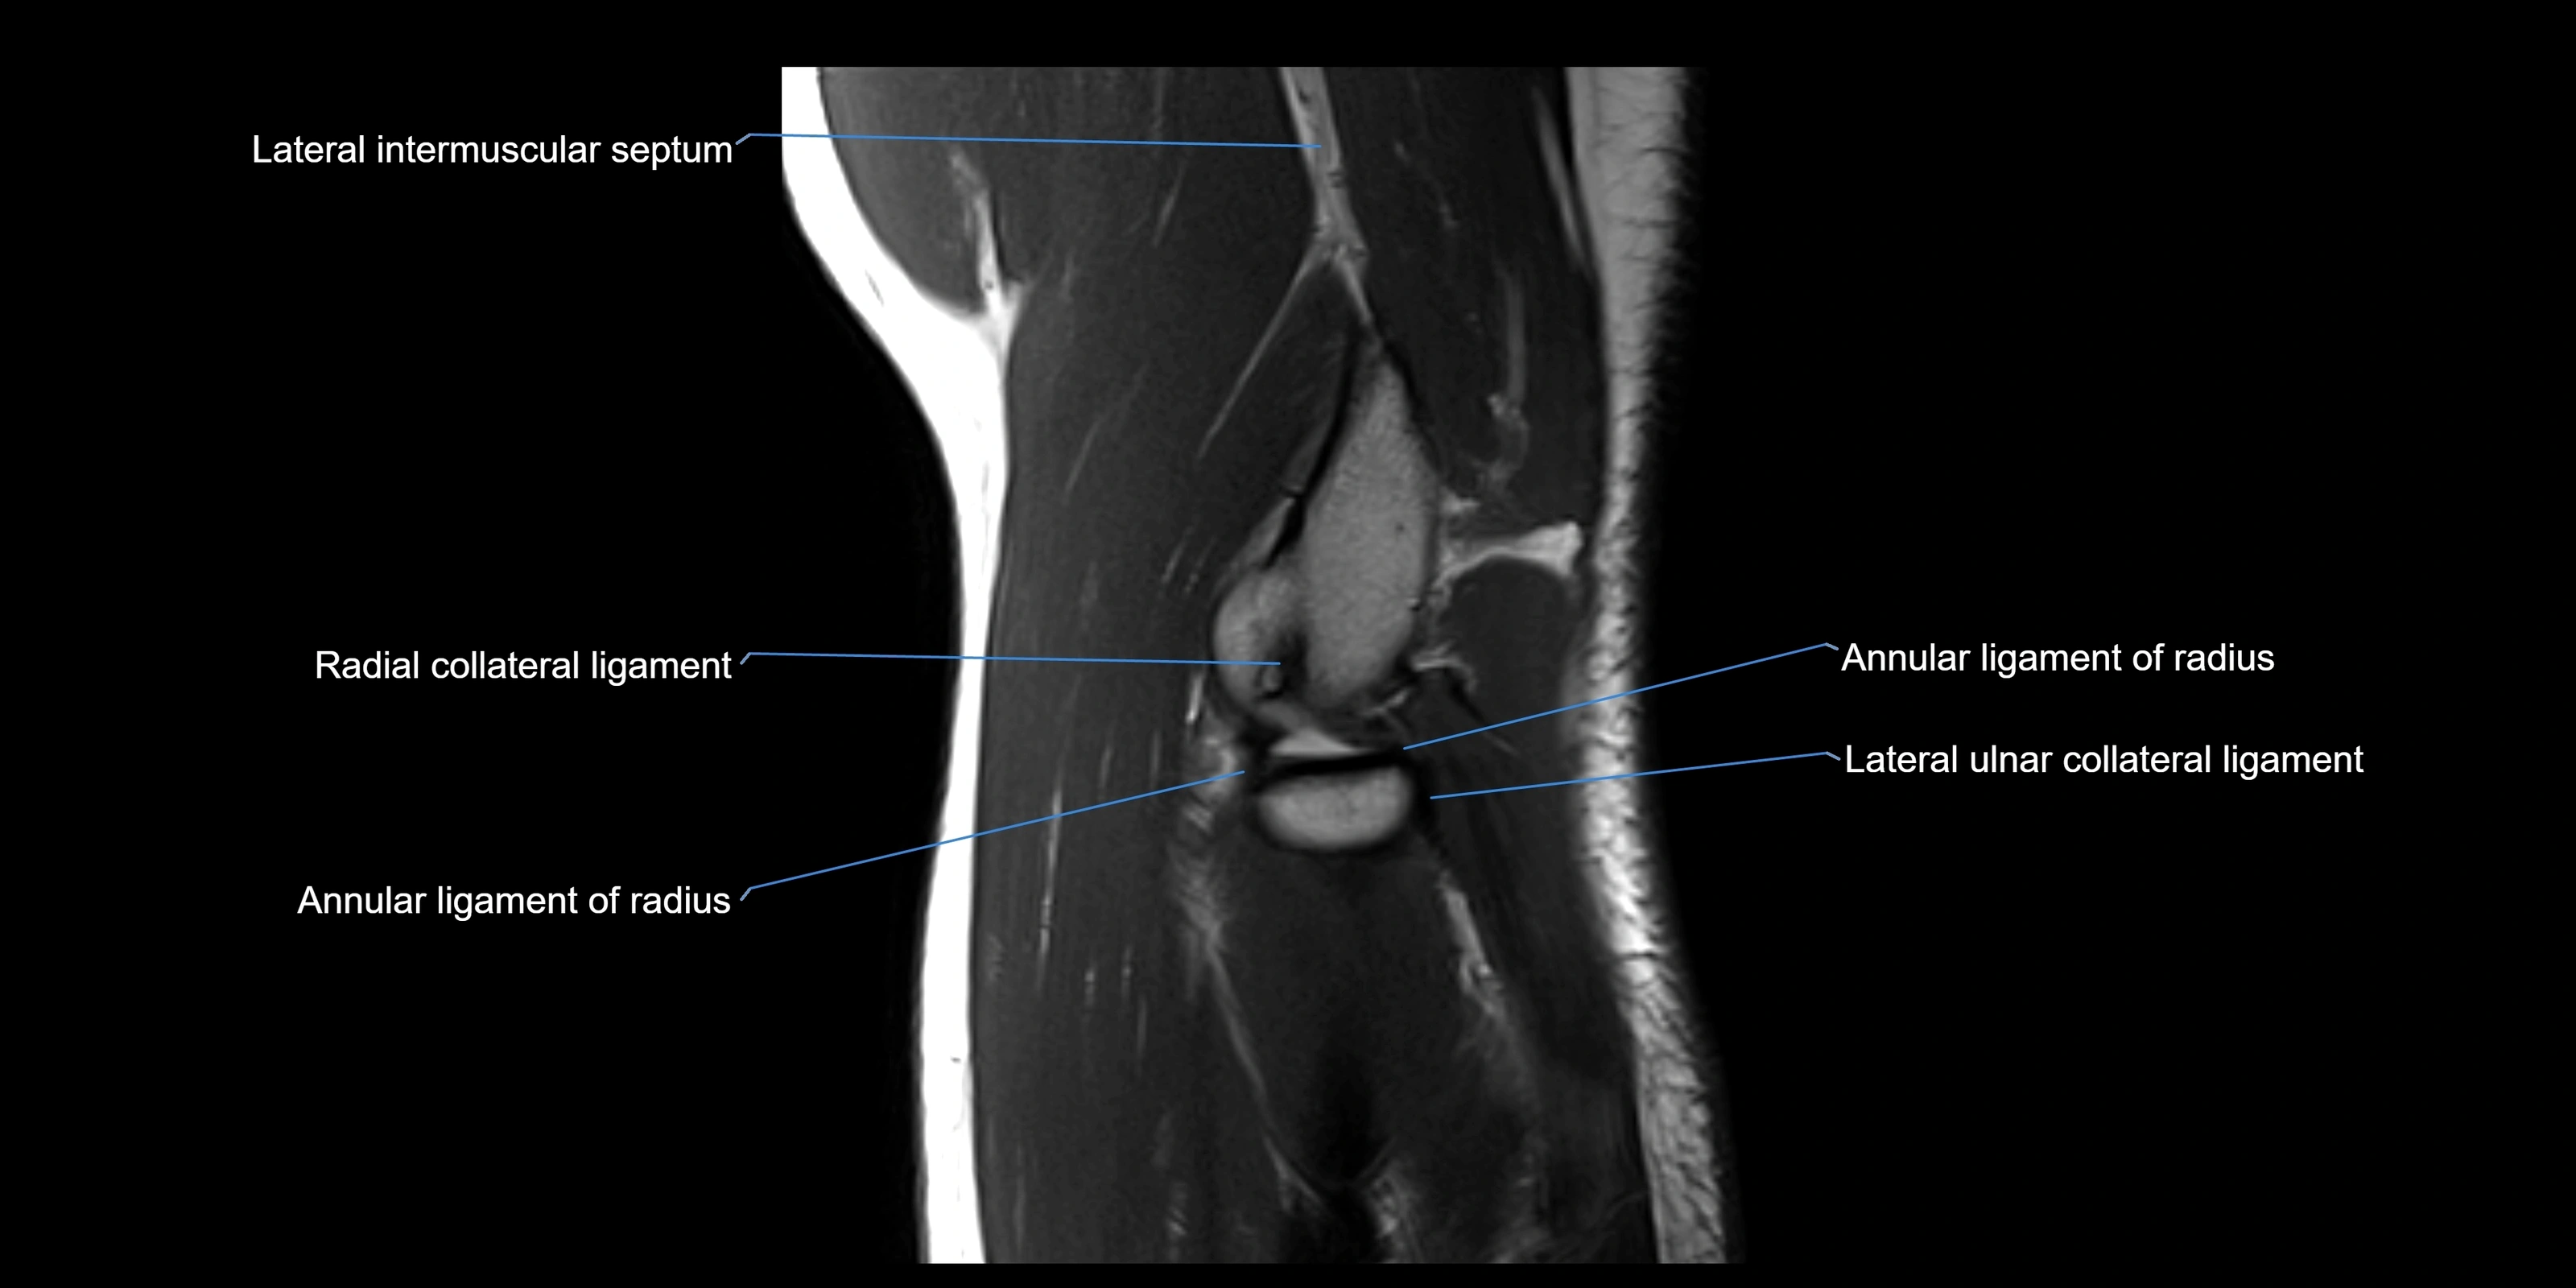

Annular ligament of radius

The annular ligament of the radius is a strong, circular band of fibers that encircles the head and neck of the radius, holding it securely against the radial notch of the ulna. It forms part of the proximal radioulnar joint, permitting smooth rotation of the radius during pronation and supination of the forearm.

The ligament acts like a collar or loop, maintaining radial head stability while allowing rotation. It is essential for forearm motion, elbow stability, and load transmission from the radius to the ulna and humerus.

Origin, Course, and Insertion

• Origin: Arises from the anterior margin of the radial notch of the ulna.

• Course: Forms a strong circular band that wraps around the radial head and neck, maintaining them within the radial notch.

• Insertion: Attaches to the posterior margin of the radial notch, completing a fibrous ring around the radial head.

• The inner surface of the ligament is lined with synovial membrane, allowing frictionless rotation.

Relations

• Superiorly: Blends with the capsule of the elbow joint.

• Inferiorly: Supported by the quadrate ligament at the neck of the radius.

• Medially: Attached to the ulnar radial notch.

• Laterally: In contact with the radial head and its articular cartilage.

• Anteriorly: Related to the radial collateral ligament of the elbow.

• Posteriorly: Continuous with the elbow joint capsule.

MRI Appearance

T1-weighted images:

• Ligament: low signal intensity (dark), appearing as a continuous band around the radial head.

• Adjacent fat and marrow: bright, creating contrast with the ligament.

• Thickening or disruption indicates injury or fibrosis.

• Joint capsule and synovium seen as thin low-signal lines contiguous with ligament margins.

MRI images

image